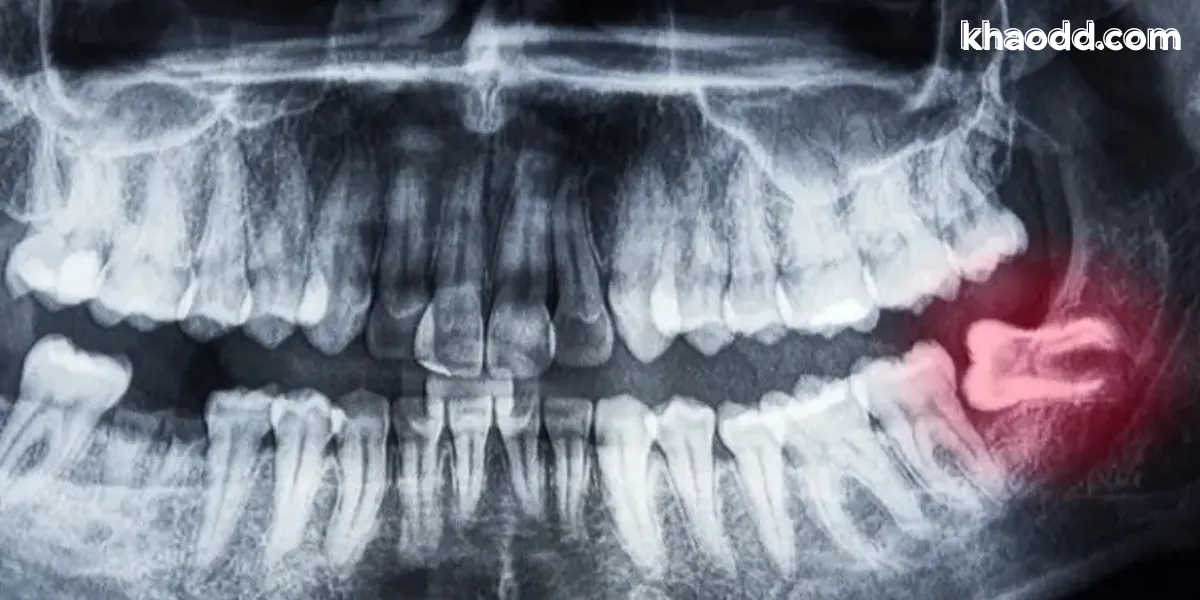

ตรวจเอ็กซเรย์ก่อนผ่า

ทันตแพทย์จะถ่ายภาพรังสีเพื่อดูตำแหน่งของฟันคุด ความลึก การเอียง การชนเส้นประสาท รวมถึงโครงสร้างกระดูกขากรรไกร เพื่อวางแผนการผ่าอย่างปลอดภัยที่สุด